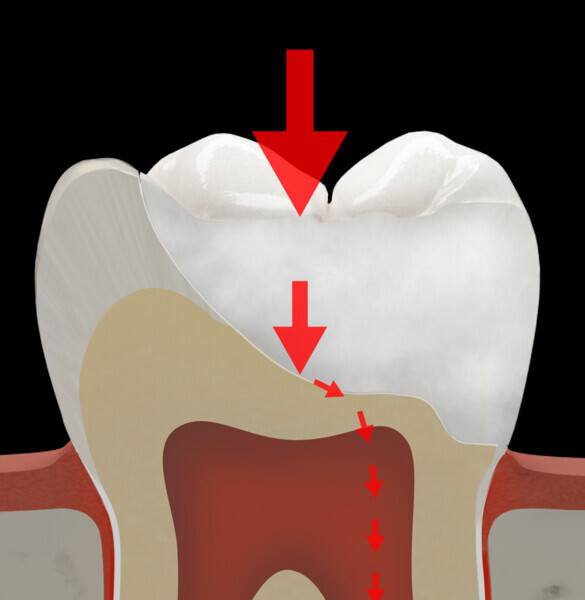

In the MiCD restorative domain, direct composite resin plays a key role owing to its fundamental advantages. These include being aesthetic, biocompatible and mercury-free, having low thermal conductivity, allowing minimally invasive restoration and supporting the dental tissue remaining after caries removal. However, long-term clinical efficacy, especially in the case of large restorations, endodontically treated teeth, cuspal restorations and large Class V restorations, is limited by the susceptibility to crack formation and propagation. The longevity of composite resin restorations is inversely proportional to their size. Larger restorations are more prone to failure, often due to fractures, especially in teeth with significant crown destruction.1

Based on the interpretation of clinical studies, fracture is the most common reason for failure of a composite restoration, followed by secondary caries and loss of retention.2–6 According to long-term studies, the failure rate of Class II cavities after ten years ranges between 15% and 20% and is mostly associated with fractures.

The limitations of direct composite resin include low fracture toughness and issues related to polymerisation shrinkage. To address these challenges, recent advancements in dental materials have highlighted the significant benefits of incorporating fibres into both direct and indirect composite resin restorative materials.

The first step in the MiCD Fiber Filling 4R protocol involves recognising the tooth status, existing occlusal forces and potential tooth preparation design. This starts with a thorough assessment of the patient’s dental condition, occlusal patterns and occlusal contact mapping using articulating paper of suitable thickness and the progressive colour transfer technique. Every tooth has its own stress pattern, and each contact location on a tooth behaves differently under stress. Recognising these patterns is vital for designing a restoration that avoids potential failure in the long term. Additionally, designing the restoration with tooth and restoration reinforcement in mind helps address specific structural requirements and challenges, ensuring that the final outcome is both functional and durable.

The second step focuses on reinforcing the restoration through careful fibre and FRC selection and placement. Tooth preparation should involve minimal removal of tooth structure to preserve as much natural tooth as possible in preparing the cavity for the restoration. Fibres or layers of FRC (flowable, paste, cube, etc.) are then strategically placed within the prepared tooth and composite material to reinforce areas susceptible to high stress and occlusal forces based on occlusal contact mapping. This strategic selection and placement of fibres and layers of FRC is crucial for enhancing the strength and longevity of the restoration.